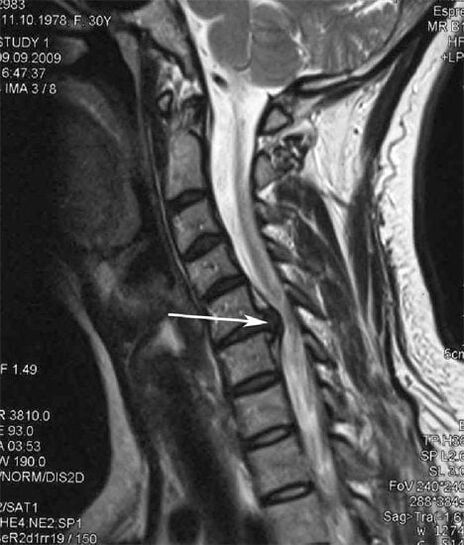

Sākotnējās stadijās osteohondrozi atklāj, izmantojot MRI. Vēlāk patoloģiju var diagnosticēt, izmantojot radiogrāfiju. Uz mugurkaula kakla daļas rentgenogrammām kļūst pamanāms attāluma samazināšanās starp skriemeļiem, patoloģiskas izmaiņas fasešu locītavās un osteofitoze.

Daudzi cilvēki sūdzas, ka nevar pagriezt kaklu stipru sāpju dēļ, kas parādās, pēkšņi paceļot kaut ko smagu. Šī parādība norāda uz diska trūces veidošanos. Muguras, kakla un augšējo ekstremitāšu sāpju cēlonis ir vienas no muguras smadzenēm izplūstošās nervu saknīšu saspiešana.

Sāpes mugurā un mugurkaulā var būt viena no agrīnām multiplās sklerozes, centrālās nervu sistēmas demielinizējošas slimības, pazīmēm. Cilvēkiem ar šo patoloģiju attīstās tā sauktais Lhermitte simptoms. To raksturo elektriskās strāvas trieciena sajūta pakausī, kas rodas, noliekot galvu uz priekšu.